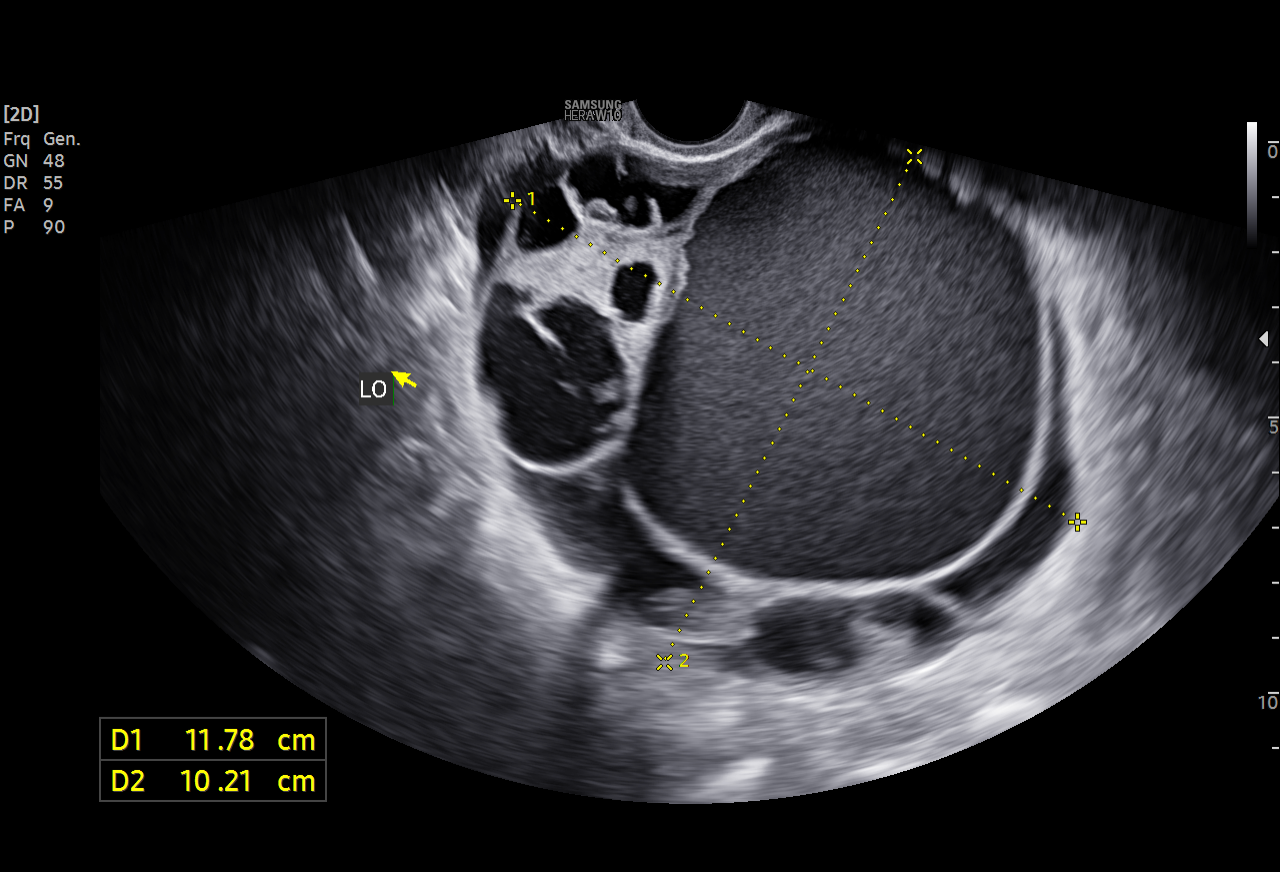

- 초음파 이미지(원천:PNG – 라벨링:JSON)

| 원천데이터 | 라벨링데이터 |

|---|---|

![]() |